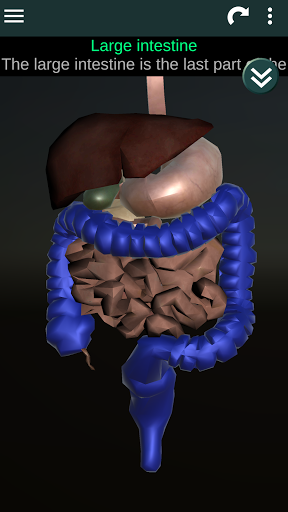

Показує 3D анатомічну модель основні органи людського тіла та опис кожного з них.

* Травна система, включаючи шлунок, тонку кишку, товсту кишку та анімацію цієї системи.

* Описи кожного органу.